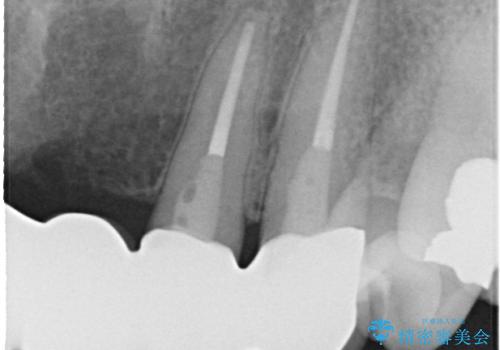

- 仮歯の製作、古い土台(メタルコア)の除去まで行い、根管治療は専門医に依頼

→根管治療終了後、ファイバーコアを築造し、新しいセラミックブリッジを製作した。

一見きれいにはいっているセラミックも、はずして中の状態をみるとひどいことが多い。これは、中の土台の状態や処理のクオリティは、短期的には問題を起こしづらく、患者さんには見えない部分だからです。